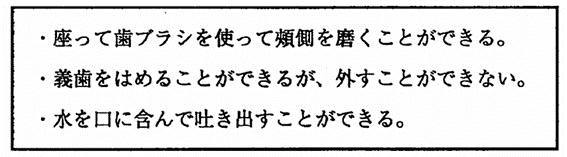

84歳の男性.脳梗塞で右側の半身麻揮がある。患者の口腔清掃の状況を図に示す。BDR指標で正しいのはどれか。1つ選べ。

B – D – R

a. a1 – b – a

b. a2 – b – b

c. b1 – b – b

d. b2 – a – b

解答を見る

c